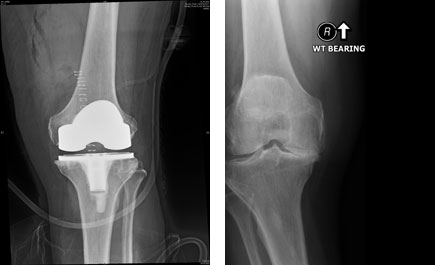

نجاح استبدال مفصلي الركبة لسبعيني بمجموعة الحبيب

أجري في المجمع الطبي بالعليا التابع لمجموعة د. سليمان الحبيب عمليتي استبدال مفصلي الركبة لمريض يبلغ من العمر 70 عاماً كان يعاني من آلام حادة في الركبتين وصعوبة في المشي والحركة مما أثر على ممارسة حياته الطبيعية طيلة 6 سنوات. ذكر ذلك الدكتور طارق حسن طبيب جراحة العظام والمفاصل الحاصل على الزمالة البريطانية، وقال: إن المريض تم تشخيصه من خلال إجراء الفحوصات الإشعاعية X-RAY حيث تبين وجود احتكاك متقدم من الدرجة الرابعة وذلك من خلال التآكل الشديد للغضاريف المانعة للاحتكاك في الركبتين. كما تمت متابعة حالة المريض الصحية مع طبيب أمراض القلب ضمن جدول التشخيص العلاجي ولمزيد من الاطمئنان. وأوضح د. طارق أنه بعد دراسة الوضع الصحي للمريض والاطلاع على حالة مفصلي الركبة تم اتخاذ قرار إجراء العملية واختيار أفضل المفاصل الصناعية بالعالم وهى من نوع (ZIMMER) لإنهاء معاناة المريض من الألم وعودة حياته بشكل طبيعي.

وعن استبدال مفصل الركبة اليسرى قال د. طارق: إن العملية استغرقت أيضاً الساعتين وتم إجراؤها بعد مرور أسبوعين من العملية الأولى. مؤكداً أن إجراء كل عملية على حدة أفضل ومن شأنه منع حدوث أي مضاعفات يمكن أن تحدث. وفي الختام قال د. طارق: إن العمليتين أجريتا بنجاح تام ولله الحمد وخرج المريض بعد 5 أيام وهو بصحة طيبة وقد انتهت لديه كافة الأعراض السابق ذكرها وسيعود لممارسة حياته بشكل طبيعي بعد إنهاء فترة العلاج الطبيعي وسيقوم المريض بأداء واجباته اليومية وأداء الصلاة بصورة اعتيادية